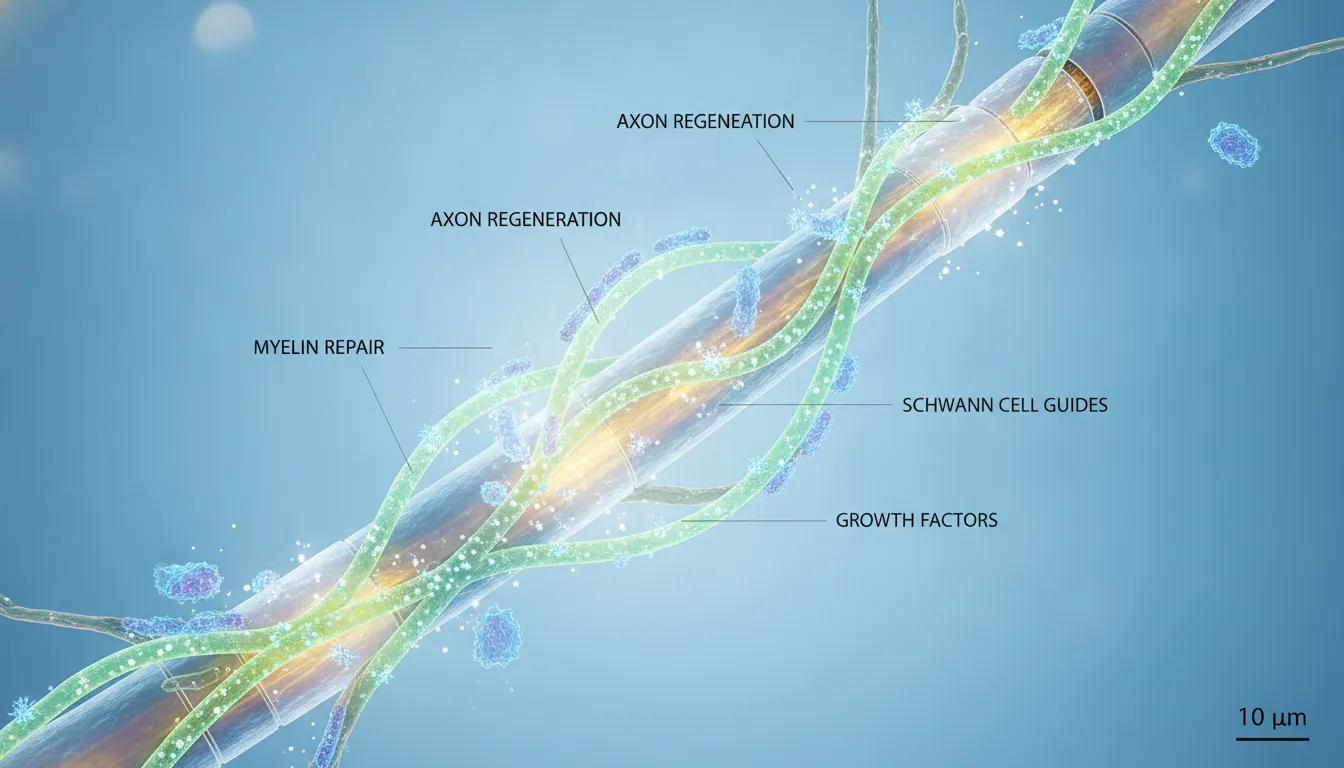

For those looking for a solution that goes beyond symptom management, regenerative medicine offers a promising approach. These therapies aim to support your body’s own natural healing processes. For instance, PRP therapy uses a concentration of your own blood platelets to reduce inflammation and encourage tissue repair within the knee. Similarly, advanced stem cell treatments introduce powerful, versatile cells into the joint to help manage inflammation and promote a healthier joint environment. These innovative therapies focus on addressing the underlying issues of arthritis, offering the potential for more sustained improvement in pain and function.

Regenerative medicine offers a different path. Instead of just managing symptoms, the goal is to work with your body’s own powerful healing abilities to repair the damage from within. This approach uses biological materials to help restore function and regenerate tissue in your knee. By creating the right environment for your cells to repair damaged cartilage and reduce chronic inflammation, regenerative treatments aim to provide lasting relief and improve your joint’s health. It’s a proactive strategy that supports your body’s natural processes, potentially helping you avoid invasive surgery and get back to the activities you love.

A Look at Stem Cell Therapy

One of the most promising regenerative treatments for knee arthritis is stem cell therapy. This procedure involves introducing mesenchymal stem cells (MSCs) directly into the knee joint. Think of these cells as your body’s master repair crew. Once in the joint, they have the potential to do several important jobs at once. They can help significantly reduce the inflammation that causes so much pain and stiffness. At the same time, they can send signals that support the repair of your damaged cartilage and surrounding tissues, addressing the arthritis at its source.

The Benefits of Exosome Treatments

To make regenerative treatments even more effective, we often use exosomes. Exosomes are tiny vesicles derived from stem cells that act like messengers, carrying vital instructions from one cell to another. They are packed with growth factors and signaling molecules that are crucial for healing. When introduced into the knee, these exosomes deliver their cargo directly to your cells, telling them to begin repairing tissue and calming inflammation. They essentially enhance the communication within the joint, making the entire regenerative process more focused and efficient.